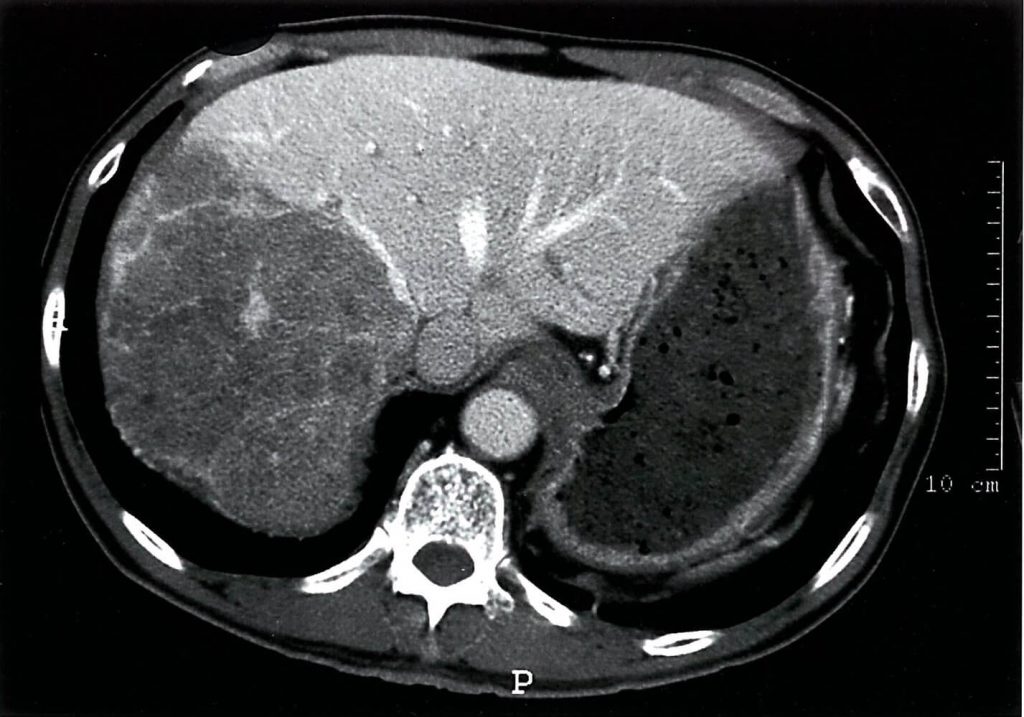

کارسینوم هپاتوسلولار (HCC)

کارسینوم هپاتوسلولار (HepatoCellular Carcinoma=HCC) تومور بدخیم کبد است که معمولاً مفرد و تنها (solitary) میباشد. این بدخیمی به صورت اولیه در بیماران با سیروز کبدی و هپاتیت مزمن به وجود میآید. اساساً این بیماری، یک تشخیص تصادفی است که از طریق سونوگرافی یا سطح بالای آلفا فتو پروتئین (a-fetoprotein) تشخیص داده میشود.